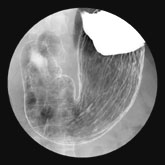

○ 胃がん

胃がん検診の受け方

市町村から送られてくる「受診券」と「自己負担金」をお持ちになって来院ください。簡単な問診と、胃バリウム検査にて行います(胃カメラ検査では実施できない決まりになっています)。